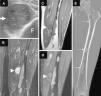

Clinical ObservationWe report the case of a 45-year-old man who presented with a hard, painless mass in the medial surface of his left thigh that had grown slowly in recent months. He was referred to our center with musculoskeletal ultrasound, which documented an intramuscular lesion, in the distal third of his left thigh, with well-defined borders, heterogeneous echogenicity and good posterior transmission (Fig. 1A). Magnetic resonance imaging (MRI) demonstrated a solid intramuscular mass measuring 3cm in the vastus medialis muscle; it was hypointense in T1-weighted sequences and hyperintense in T2, with no calcifications, and with a peripheral and patchy enhancement in its interior after the administration of intravenous gadolinium; another 1-cm intramuscular lesion was observed with characteristics similar to those of the image, in the left great adductor muscle, but it was not clinically palpable. In bone, with enhancement, we identified expansive diaphyseal intramedullary lesions in left femur and left tibia, consistent with fibrous dysplasia. Computed tomography (CT) of lower limbs showed the typical ground glass pattern of fibrous dysplasia (Fig. 1B–E).

(A) Axial image of left thigh ultrasound, showing an intramuscular soft tissue mass, that is hypoechoic and heterogenic (arrow), compatible with a solid lesion. (B–D) Coronal views from MRI of left thigh, showing the well-defined, markedly hyperintense, intramuscular mass in the STIR sequence (arrowhead in B), hypointense in T1 (arrow in C) and with heterogeneous enhancement after intravenous gadolinium administration in the T1 postcontrast sequence, with fat saturation (arrowhead in D), compatible with myxoma. Bone lesions can also be visualized in femur with diffuse enhancement after contrast administration. (E) Coronal CT view of femur with bone window, which shows the bone lesions with increased density, with a “ground glass” pattern typical of fibrous dysplasia (small arrows). CT, computed tomography; F, femur; MRI, magnetic resonance imaging; STIR, short tau inversion recovery.

The characteristics of the bone lesions were compatible with polyostotic fibrous dysplasia, and the coexistence with intramuscular soft tissue lesions were suggestive of Mazabraud's syndrome.